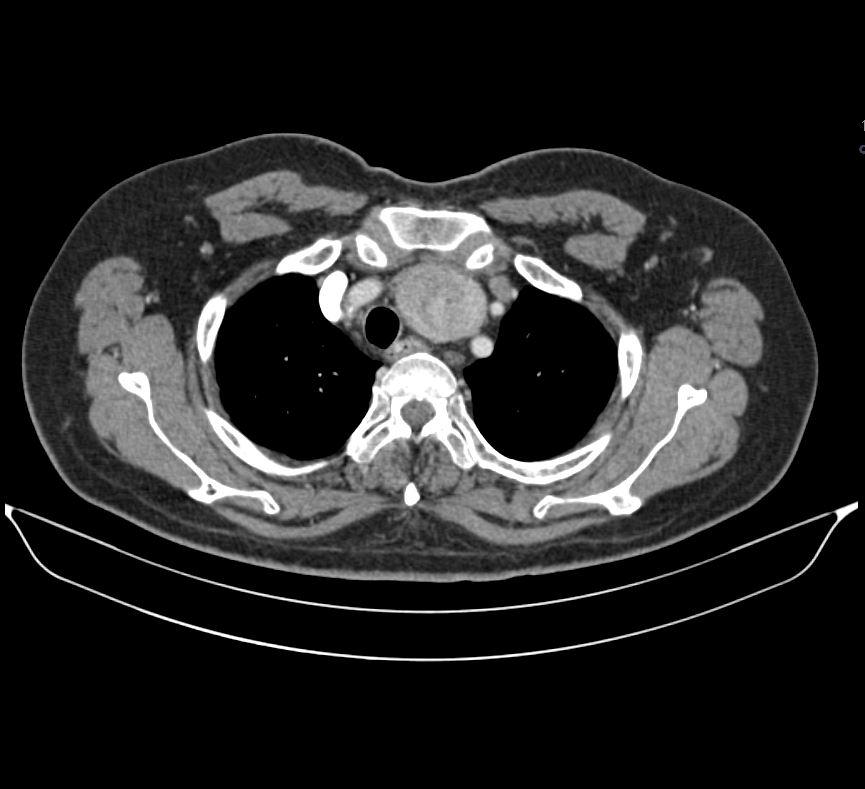

Case of the Week 18 2017 *57-year-old male with fever, confusion, and headache. What is the most likely diagnosis? Answer Answer: Substernal goitre Kategori:Cases Önceki yazı Case of the Week 14 2017 Sonraki yazı Case of the Week 15 2017